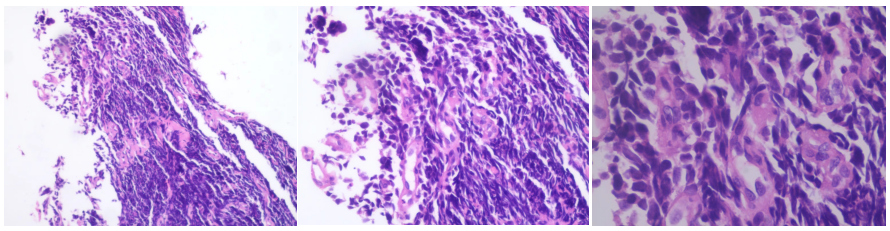

▌病理结果

2021-12-10病理结果:(右上叶开口粘膜)肺小细胞癌。

免疫组化结果:TTF-1(+),NapsinA(-),P63(-),CK5/6(-),P40(-),Syn(+),CgA(+),CD56(+),LCA(-),SATB2(-),Ki-67(热区>95%+),p53(+),CK(+)。